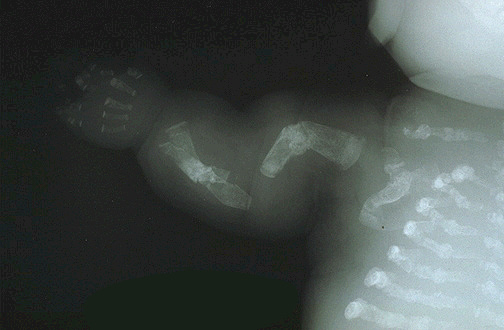

Radiograph of a premature infant with the perinatal lethal form of osteogenesis imperfecta. Skull is relatively large and unmineralized, thoracic cavity is small, long bones of arms and legs are short and deformed, vertebral bodies are lattened. All bones are undermineralized.